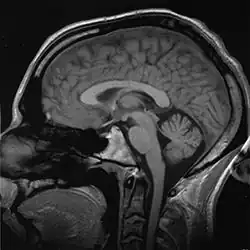

También se ha vuelto posible el estudio del cerebro vivo y los investigadores ahora pueden observar la maquinaria de la toma de decisiones trabajando. Un experimento en este campo fue conducido por Benjamín Libet en los años 1980, en el cual él les pedía a sujetos escoger un momento cualquiera para agitar su muñeca mientras él lo asociaba con la actividad cerebral.

Libet descubrió que la actividad cerebral inconsciente que llevaba a la decisión consciente de mover su muñeca comenzaba medio segundo antes de que el sujeto conscientemente decidiera moverla. Esta masa de carga eléctrica ha sido llamada potencial de estar listo (o potencial de preparación). Los descubrimientos de Libet sugieren que las decisiones tomadas por un sujeto son primero hechas en un universo inconsciente y después son traducidas a una “decisión consciente”, y la creencia del sujeto de que esto ocurrió bajo su voluntad se debe únicamente a la visión retrospectiva del evento. Por otro lado, Libet todavía encuentra espacio en su modelo para el libre albedrío, en la noción del poder del veto: de acuerdo con este modelo, los impulsos inconscientes que ocasionarán un acto voluble pueden ser suprimidos por los esfuerzos conscientes del sujeto. Cabe acotar que esto no significa que Libet crea que las acciones inconscientemente incentivadas necesitan la ratificación de la consciencia, sino que, más bien, la consciencia retiene el poder de negar la actualización de los impulsos inconscientes.[40][41]

Un experimento relacionado, realizado después por el doctor Álvaro Pascual-Leone, se basaba en preguntar a los sujetos qué mano querían mover. Encontró que, estimulando diferentes hemisferios del cerebro usando campos magnéticos, era posible influenciar fuertemente en la escogencia de la mano. Normalmente la gente que opta por la mano derecha escogería mover dicha mano el 60 % del tiempo, pero cuando el hemisferio derecho era estimulado, escogerían la mano izquierda en un 80 % de las situaciones; el hemisferio derecho del cerebro es responsable del lado izquierdo del cuerpo, y viceversa. A pesar de la influencia externa en la toma de decisiones, los sujetos continuaban reportando que creían haber tomado la decisión libremente. El mismo Libet,[42] sin embargo, no interpreta su experimento como experiencia de la ineficacia del libre albedrío consciente —él señala que a pesar de la tendencia que dice que al presionar un botón, y acumular por 500 milisegundos, el consciente retendrá el derecho a vetar esa acción en los últimos milisegundos—. Se puede comparar con un jugador de golf, que puede mover el putter varias veces antes de acertar. Si nos basamos en esto, la acción simplemente recibe una estampa de aprobación en el último milisegundo. También planeando las actividades del día de mañana, o para dentro de una hora, el interruptor de los milisegundos es insignificante.

Puede, o no, ser posible alcanzar una realización científica final involucrando la posibilidad del libre albedrío adentrándonos en los orígenes de nuestros pensamientos conscientes. En el punto de vista científico, toda experiencia consciente es contingente hacia las neuronas —un golpe fuerte en la cabeza puede servir como demostración a este punto, así como casos documentados de lesiones neurológicas.[43] El cerebro consiste en miles de millones de neuronas, con mil billones de conexiones entre ellas. En un nivel bioquímico, la tarea principal de una neurona es propagar impulsos electro-químicos a otras neuronas formando un “circuito integrado” que constantemente recibe información de los sentidos (vista, olor, tacto y gusto) y devolviendo información para controlar músculos y órganos. Solo el 10 % de las neuronas en el sistema nervioso tratan con los impulsos sensoriales y con el control de músculos; las neuronas sobrantes sirven para integrar, refinar y procesar señales de entrada o salida.

La experiencia del libre albedrío es así conceptualizada surgiendo de alguna combinación de estas neuronas, pero ¿cómo llegamos a esta acumulación de neuronas, que son finos hilos de grasa con el potencial de recibir impulsos eléctricos, pueden dar poder a nuestro consciente, emociones y sentimientos? ¿Cómo puede ser que este concepto de “yo” y nuestro libre albedrío puede controlar neuronas y nuestro comportamiento, y el cerebro es meramente una sopa tibia de grasa, colesterol y neurotransmisores? Este misterio sin resolver domina el debate moderno sobre la existencia de nuestra conciencia y la posibilidad del libre albedrío.

En los años 1970, Libet estuvo involucrado en los estudios de la actividad neural y la "sensación de umbral". Estas investigaciones trataban de determinar la secuencia de activación en sitios específicos del cerebro requerida para desencadenar acciones voluntarias tales como el pulsado de un botón, utilizando equipos electroencefalográficos. Un famoso experimento —luego reproducido muchas veces por otros grupos— demostró que eventos cerebrales inconscientes (observables como potenciales eléctricos, llamados potenciales de preparación [en inglés readiness potential]) realmente preceden en un lapso variable (de 0.3 hasta varios segundos) la sensación consciente de haber tomado una decisión voluntaria en preparación de una acción motora —como el pulsado de un botón—.

Ahora bien conocido en neurología, el llamado 'Bereitschaftspotential' (BP en idioma alemán, 'readiness potential' en inglés), también llamado 'potencial premotor, es una medida de la actividad en el córtex motor y el área motora suplementaria en el cerebro ocupado en la preparación de un movimiento muscular voluntario. Es una manifestación de la contribución cortical al planeamiento del movimiento voluntario. Fue registrado y reportado ya en 1964 por Hans Helmut Kornhuber y Lüder Deecke en la University of Freiburg en Alemania. La publicación completa apareció en 1965 luego de muchos experimentos usados como control.[44]

Estas observaciones indican que los procesos neurológicos inconscientes preceden y potencialmente causan tanto la sensación de haber realizado una decisión por propia voluntad como el mismo acto motor.[45]

La conclusión derivada por Libet de estas observaciones es que los procesos cerebrales determinan las decisiones, luego percibidas como propias subjetivamente por el mismo cerebro a través del fenómeno de la consciencia (awareness). Libet solamente considera como posible la idea de libre albedrío en su noción de veto —la capacidad de la actividad consciente para bloquear o abortar un acto ya iniciado—, bloqueo posible gracias al tiempo restante de algunos cientos de milisegundos entre la percepción subjetiva de la decisión y la ejecución del acto mismo. Aunque el autor no parece adherirse a esta idea. El problema, como señala John N. Gray, es que no podemos saber cuándo utilizamos el veto, por lo que nuestra experiencia subjetiva es siempre ambigua.[46]Neurología y psiquiatría